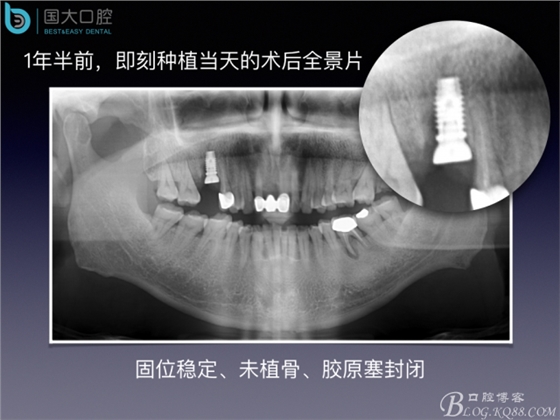

20160715154342_75439.jpeg